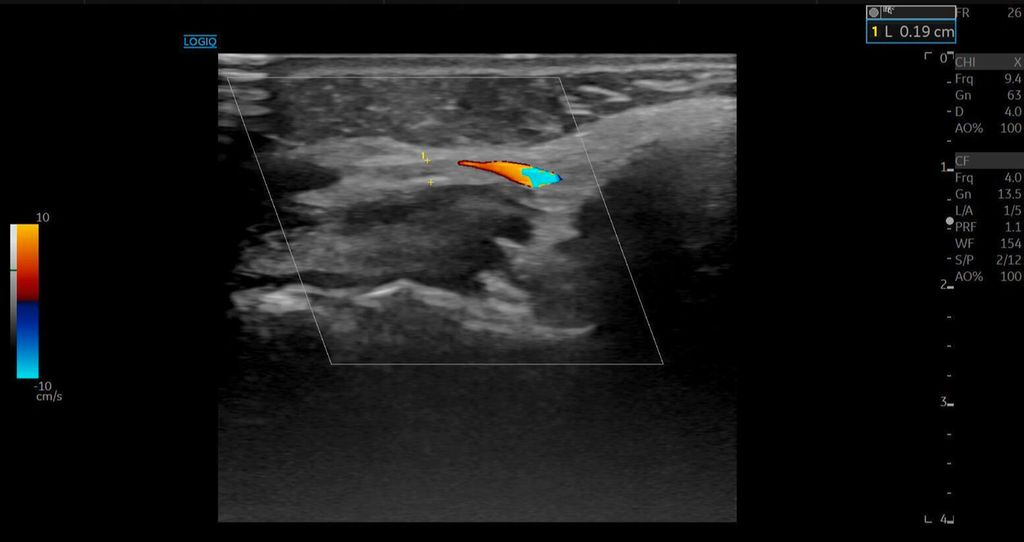

Die A. facialis imponierte beim Austritt im Bereich des Musculus masseter (oberhalb der Kieferlinie) vasospastisch mit einem maximalen Durchmesser von 1mm. Die abgeleitete systolische Spitzengeschwindigkeit betrug trotz der bestehenden Ischämie 20cm/s, ohne enddiastolische Komponente, was auf eine weitere periphere Vasokonstriktion hindeutete (Abb. 2 und 3).

Die Duplexsonografie ergab folgende Befunde (Abb. 5 und Abb. 6):

Der Durchmesser der A. angularis und A. facialis hatte sich nahezu verdoppelt.